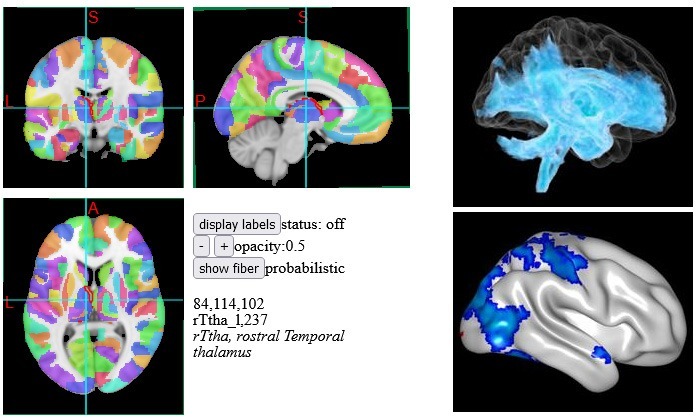

Nowadays, we can use connectomics to map out the connectivity of the thalamic lesion. Doing so revealed a large region of the brain affected by the thalamic injury. The pale blue in the top right panel of Figure 2 shows the regions of brain connected to the thalamic lesion. This is connectomics in action!

Then, we mapped the connectivity to the lesion in the left insula, as shown in Figure 3. Intriguingly, mapping the connectivity from left insula lesion showed a much smaller region of affected brain tissue compared to the effect of the thalamic lesion. Thus, the smaller thalamic lesion on the CT brain scan actually connects to a much larger region of brain than the bigger lesion in the insula does. So, connectomics allows us to visualise information that is not apparent from the standard CT brain scan. Functionally, the thalamic lesion is more consequential, even though the visible extent is smaller on the CT brain scan.

This is an significant finding and brings out the importance of connectomics. It allows us to better understand the effects of a brain injury. Typically, this is not something on the radar of a claims assessor. Let’s change that!